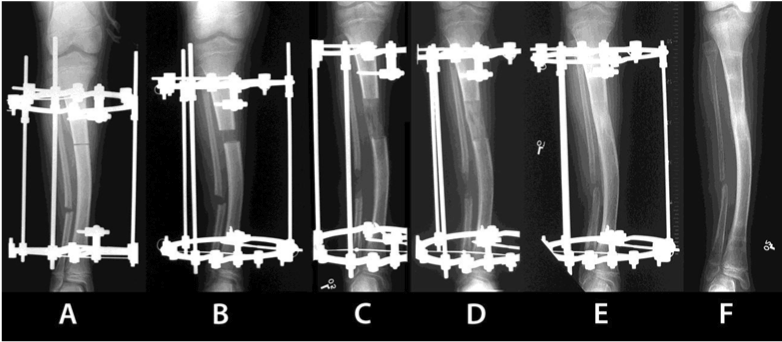

| Figure 3: Radiological representation of the distraction osteogenesis technique. A. Osteotomy is performed after the application of the external fixator; B. Initial phase of the distraction procedure. C. Elongation of the bone; D. New bone tissue formed at the distraction site; E. Radiological evidence of bone mineralization during the consolidation phase; F. Final consolidation of the lengthened bone and removal of the fixator. |